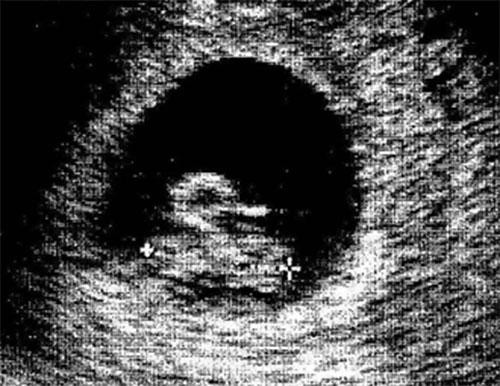

Canavar